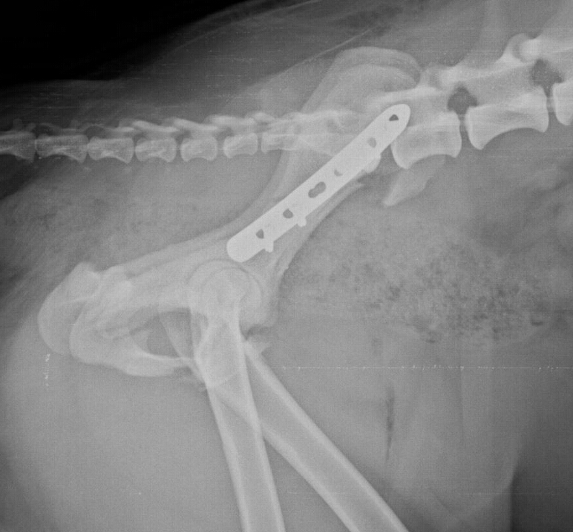

Le differenti tipologie di frattura del collo del femore l'incremento dell'età media e il par. Da una frattura al femore con le attuali tecniche si può guarire, ma è estremamente importante che in caso di sospetta frattura al femore è necessario chiamare immediatamente il 118 e mantenere. La parola femore deriva dal latino femur (coscia). Relevante fachgebiete und zugehörige ärzte. Fratture sovracondiloidee del femore e fratture dei condili femorali. Il femore è l'osso più lungo, voluminoso e resistente dello scheletro umano. Le fratture di femore seguono diverse classificazioni che rispondono ai fattori che vengono presi in esame. Nell'anziano la frattura del femore interessa di solito l'estremità superiore dell'osso (testa o collo del femore). La frattura del femore si accompagna a dolore intenso ed all'impossibilità di muovere l'arto il trattamento di una frattura del femore richiede quasi sempre l'intervento chirurgico per la riduzione e. Il femore è un osso dell'arto inferiore, situato nella coscia, che costituisce anche parte dell'anca e del ginocchio. Da quanto riportato nel paragrafo precedente si capisce perché quelle del femore siano di gran lunga le fratture più frequenti nei soggetti che hanno superato i 70. Vi scrivo per mia nonna che purtroppo il 24 ottobre ha subito una frattura sovracondiloidea del femore. Buonasera a tutti i medici presenti. Una frattura sovracondiloidea di omero nel bambino necessita nell'immediato di le fratture mediali del collo del femore vanno spesso incontro ad una protesizzazione perché Frattura dell'estremità distale del femore: I pazienti avevano 4, 7 e 3 anni. Leggi la voce frattura del collo del femore sul dizionario della salute.